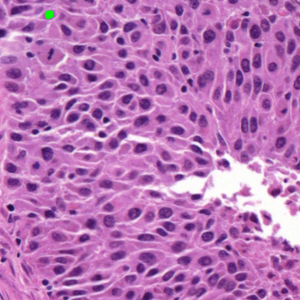

Dataset 3 consists of 50 annotated H&E-stained histological images from triple-negative breast cancer patients [74]. The images were acquired at 40× magnification using a Philips Ultra Fast Scanner (1.6RA) at the Curie Institute and contain a total of 4022 annotated cells.

Representative samples from the three datasets are shown in Fig. 1. In (a), the first frame of the synthetic video in Dataset 1 illustrates the strong illumination gradients produced by distance-dependent shading together with orientation-dependent interactions between vertex normals and the light direction. The H&E images in (b) and (c), also from Dataset 1, depict a mast cell infiltrate from a patient with non-alcoholic steatohepatitis and cirrhosis and, respectively, a sample from a patient with sclerosing polycystic adenosis of the parotid gland; the former consists primarily of purple nuclei, white cytoplasm, and pink extracellular tissue. Subfigures (d) and (e) show two examples from Dataset 2 accompanied by their ground-truth nuclei annotations, while (f) and (g) present a representative image from Dataset 3 together with its corresponding cell mask.

Figure 1: Samples from Datasets 1–3. (a) First frame of the 74-frame video in Dataset 1 (1770 × 880) with a superimposed red mesh. (b,c) H&E-stained tissue images from Dataset 1 (1000 × 750; 950 × 730). (d,e) Cell images from Dataset 2 (600 × 600) with nuclei annotations. (f,g) Image from Dataset 3 (512 × 512) with annotation.

Figure 5 shows an image from Dataset 3 with two different sets of markers. In the first case, Fig. 5(a,b), we manually placed five foreground seeds and one background seed; in the second case, Fig. 5(c,d), we slightly perturb the position of makers to test the stability of different models. Foreground and background seeds are labeled with the prefixes ‘f’ and ‘b,’ respectively, with the following number indicating their order (e.g., f2 denotes the second foreground seed). Note that there is only one background seed b1 in both cases. We then provided these to AR, SAM, and SP as markers.

Our model SP follows the selective variant from Section 5.3, with the target region number set equal to the number of markers. For SAM, we used the selective segmentation module in MATLAB 2024b. The AR model, while not requiring explicit background seeds, still needed background information; this was provided by assuming the domain outside the specified foreground was background. Since AR expects polygonal regions rather than points, we dilated the foreground seeds with a disk kernel and used the resulting regions as markers.